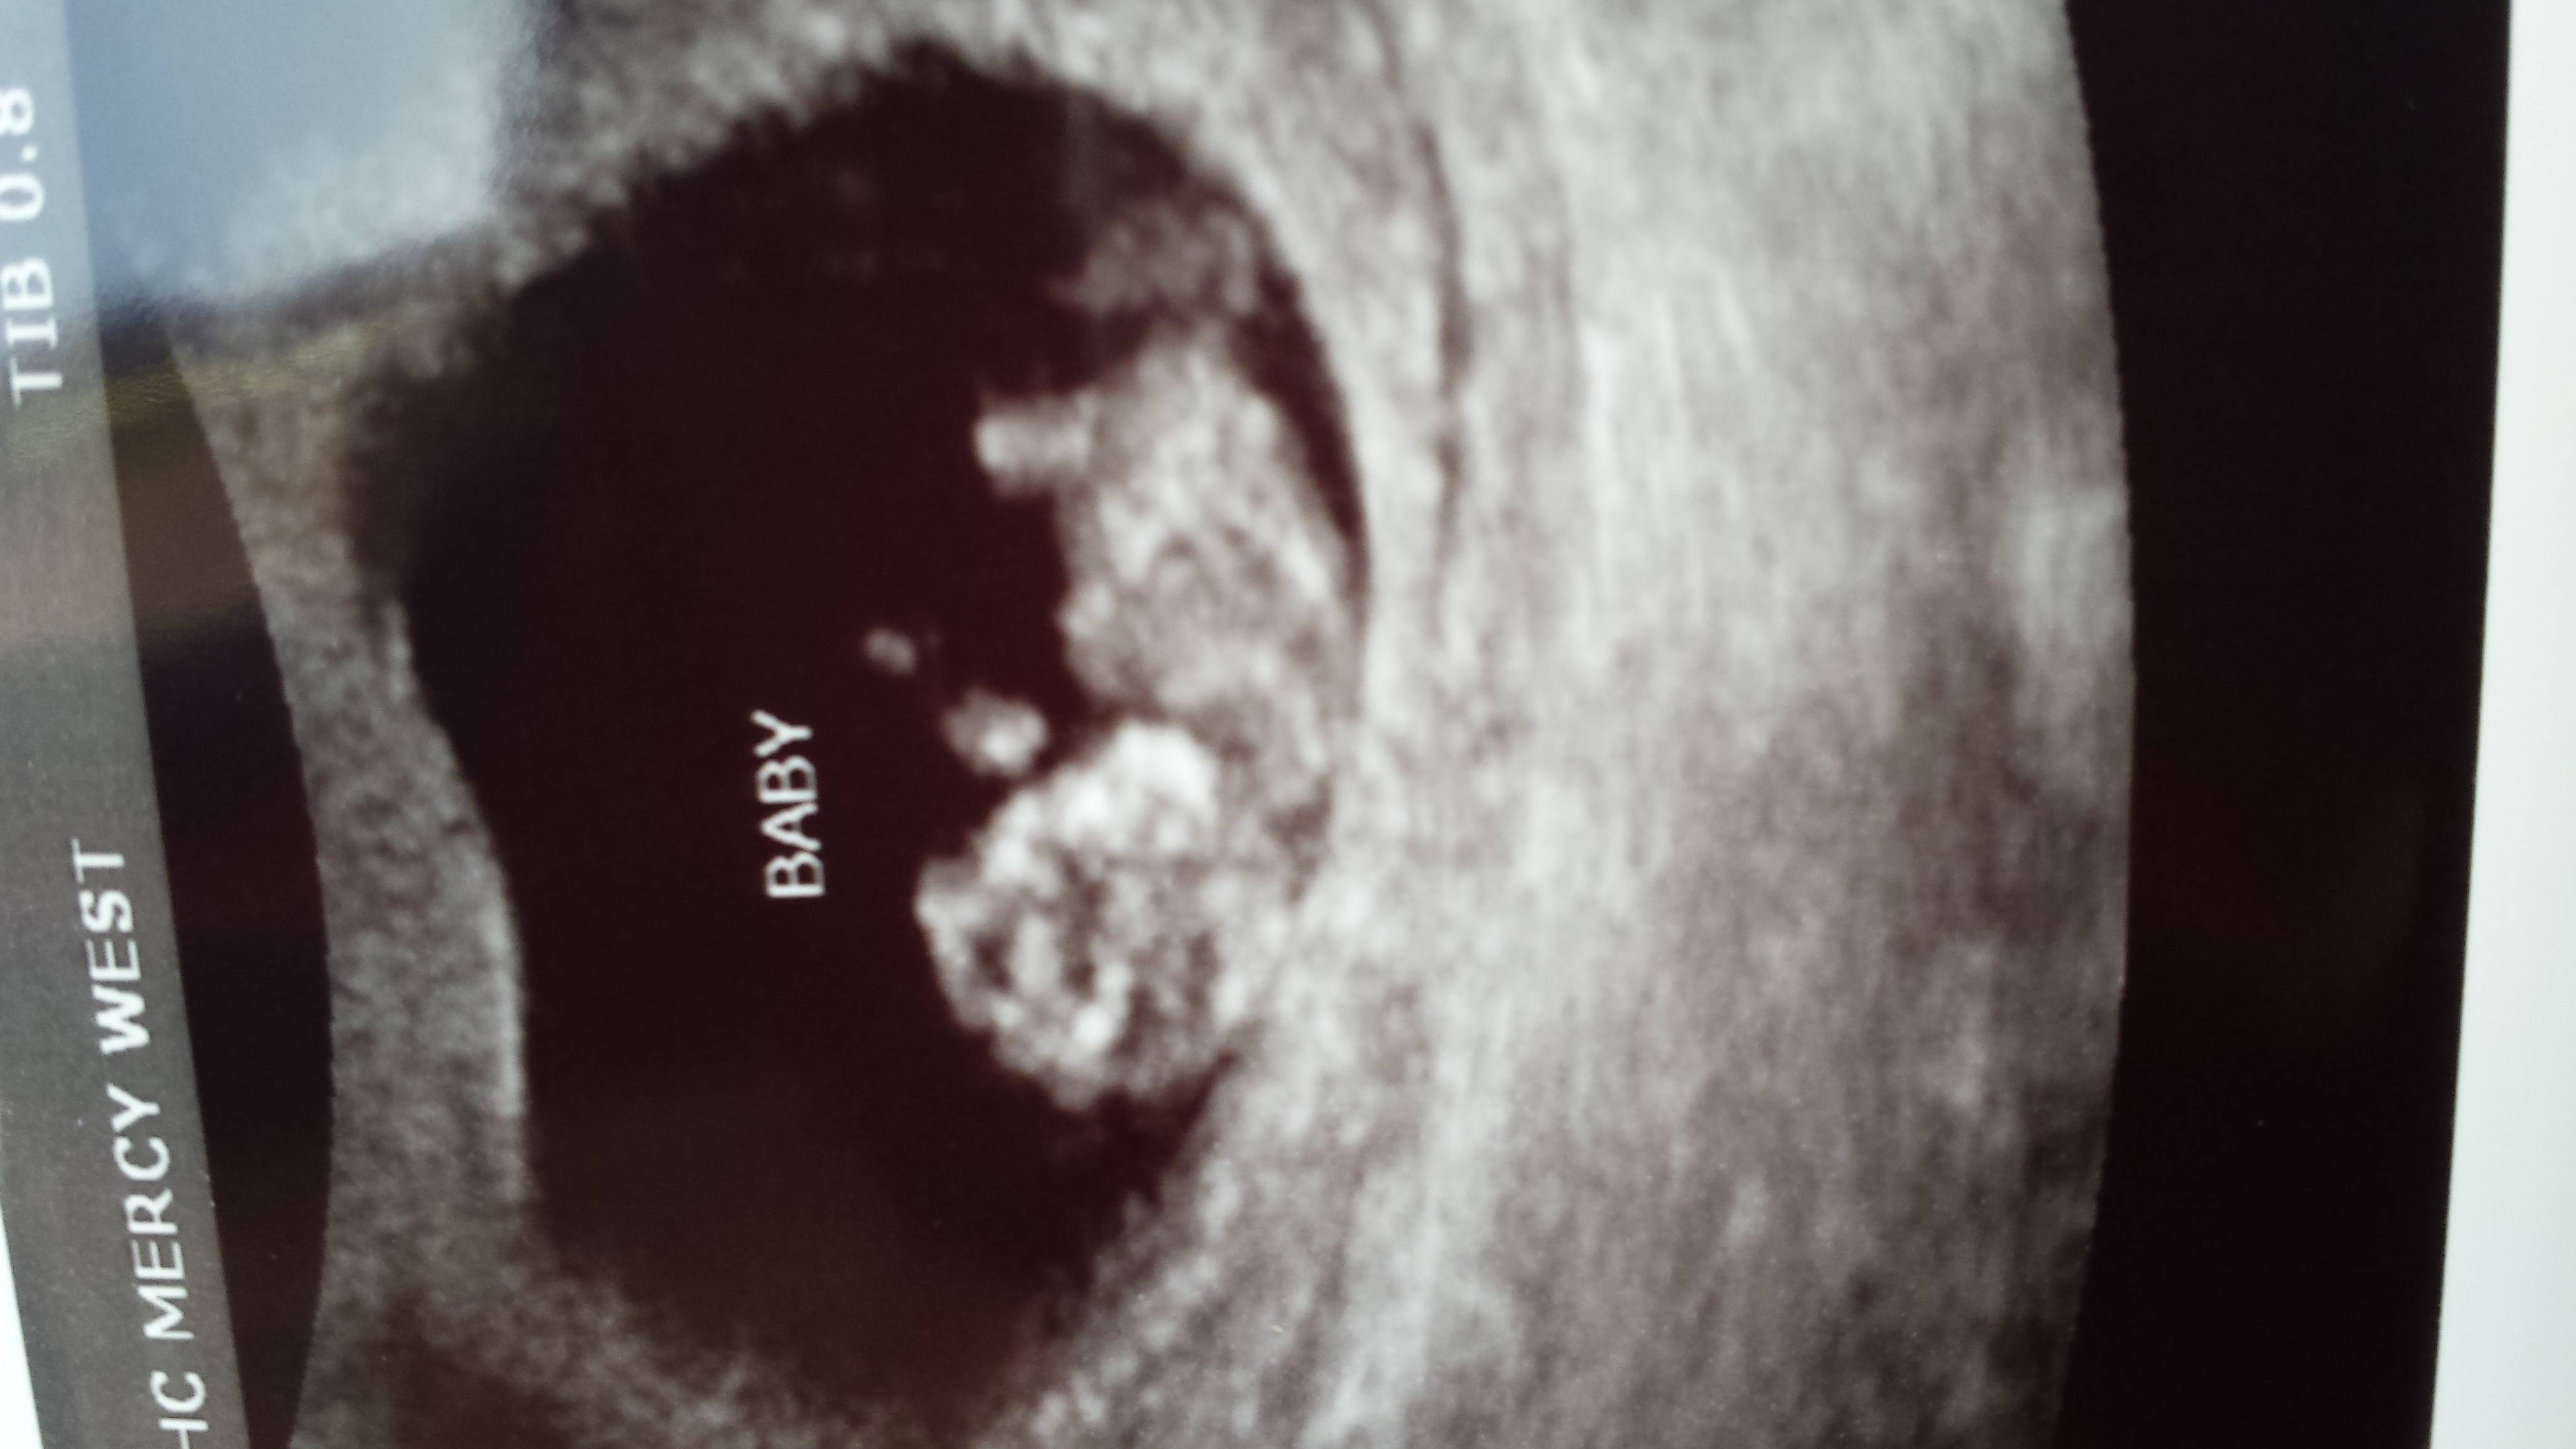

Hi all!! Haven't been on in awhile...been battling hg and have been so sick. Got our 10 week 5 day ultrasound today. Any guesses? I did a light girl sway and will be in love whether girl or boy!!Attachment 18216

Anything before 12 weeks is too early. 13 weeks is even better for a gender guess.

That's what I figured! I won't get another one until 20 weeks.

too soon to say but pretty baby.